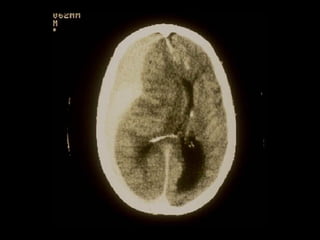

HEMORAGIILE SUBARAHNOIDIENEHEMORAGIILE SUBARAHNOIDIENE

 Se evidenţiază prin examen CT >> sânge în

spaţiul subarahnoidian, de obicei difuz peste

ţesutul cerebral.

 Dacă există şi o hemoragie intraventriculară

majoră >> prognostic rezervat

 Dacă extinderea este limitată, posibil să nu

necesite tratament specific şi prognosticul

este bun.